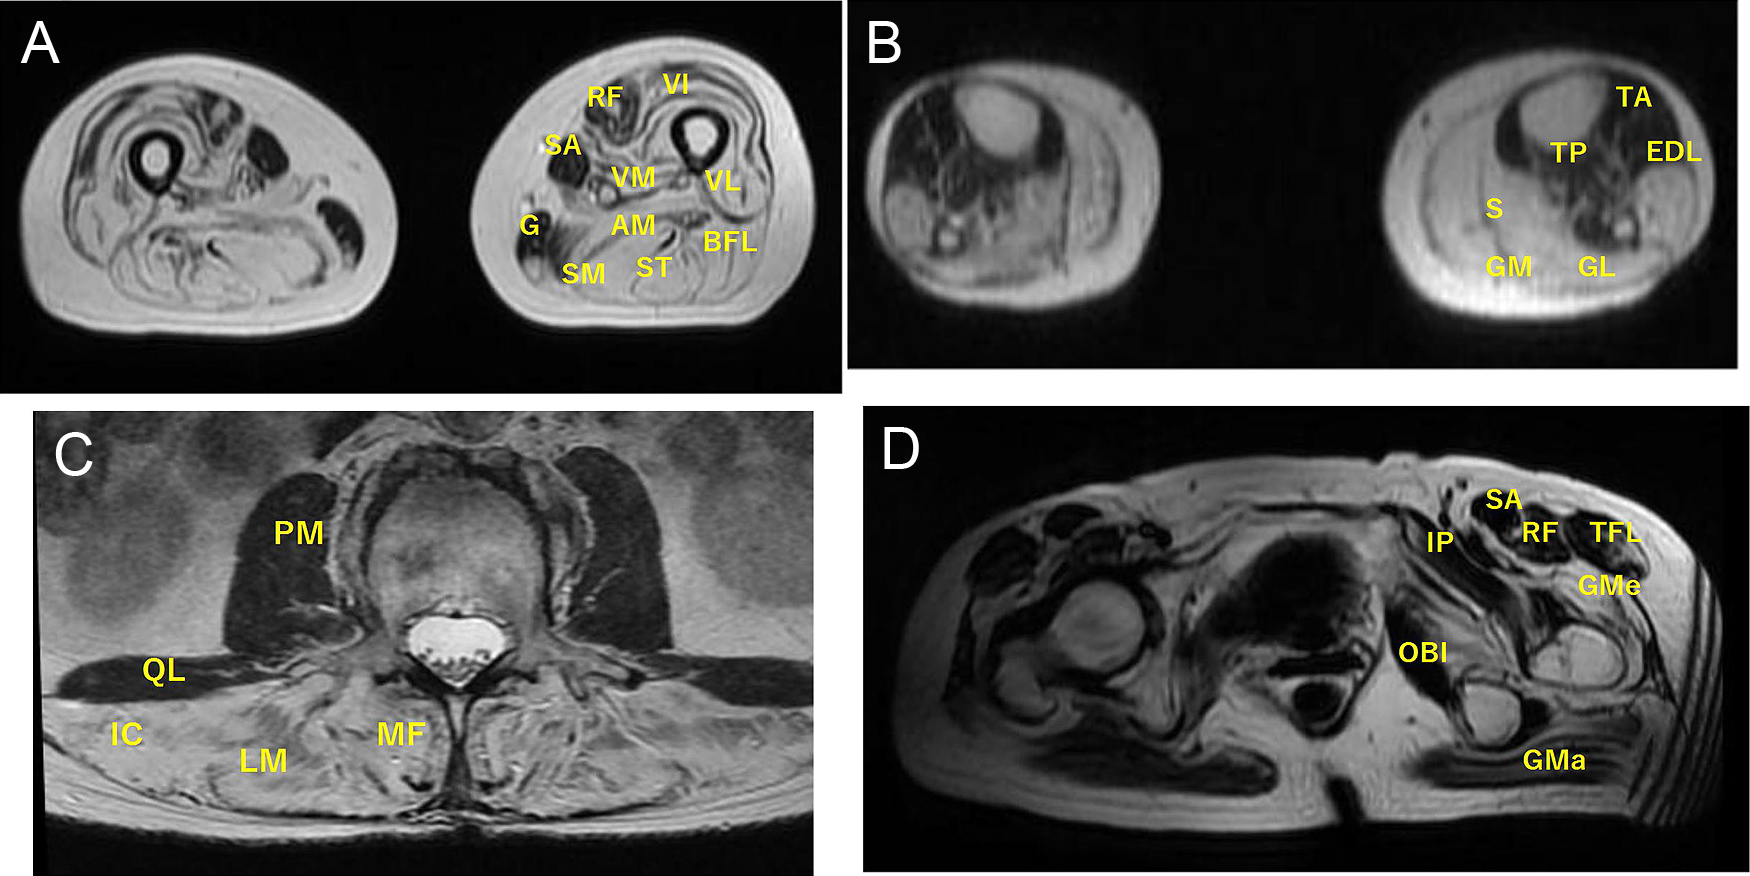

筋疾患の診療支援と教育―日本とアジアでの経験から得られた知見―

Clinical support and education in muscle disease—Experiences from Japan and Asian regions—

西野 一三

Ichizo Nishino

2026/02/13